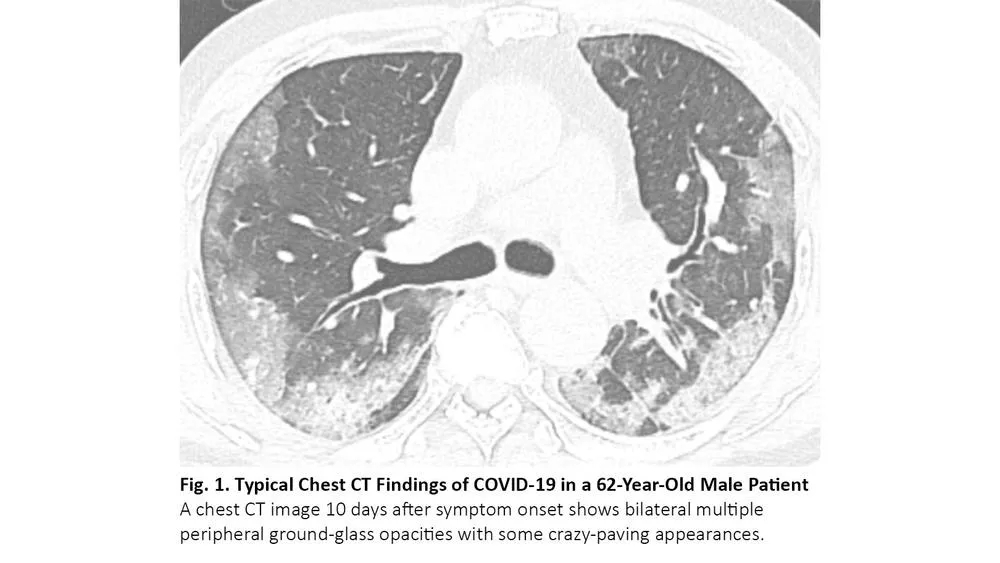

COVID-19患者的肺部CT的典型表现为双侧多发磨玻璃样影,好发于肺周3(图1)。61%~72%的COVID-19患者在症状出现后1周左右有典型CT表现,而非COVID-19患者只有不到10%人群有此类表现。4,5

图1. COVID-19患者胸部CT的典型表现

COVID-19的胸部CT可伴有局部的实质化和网状阴影(铺路石征影像表现)或其他组织性肺炎的表现,如反晕征。17% - 20%的COVID-19患者的CT与各种感染性、非感染性肺部疾病(如超敏性肺炎、肺孢子虫肺炎和弥漫性肺泡出血)难以区分(图2)。

图2. 一位67岁女性患者的胸部CT呈现COVID-19不典型特征